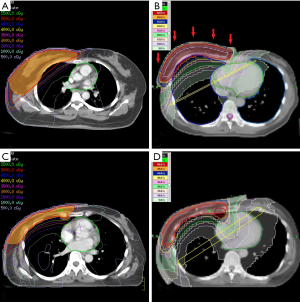

In WBRT group, 7 patients received HT and 10 patients received linear accelerated-based IMRT; in PMRT group, 6 patients received HT and 7 patients received IMRT. The detail of treatment planning and dose distribution was shown in Table 2 and Figure 3. Each patient was irradiated by a daily fraction of 2 Gy and three times of skin dose measurement was performed in three consecutive fractions. Totally, 51 times of measurement were performed in WBRT group and 39 times of measurement were performed in PMRT group.

WBRT group

Table 3 and Figure 4A showed the result of EBT3 measurement and calculated dose by TPS in WBRT group. Patients received WBRT with HT received significantly lower film dose of No.1, 2, 3, 4, 5 and 6 than those with IMRT (P=0.001, 0.001, <0.001, 0.002, <0.001, <0.001, <0.001, respectively). HT also delivered significantly lower average surface dose than IMRT did with a difference of 6.88% of prescribed dose (IMRT versus HT: 86.57% versus 79.69%, P<0.0001). The calculated dose of IMRT in different skin regions was lower than film dose; while calculated dose of HT was higher than film dose in different skin regions.

PMRT group

The result of EBT3 measurement and calculated dose in PMRT group was shown in Table 5 and Figure 4B. The mean film doses delivered by IMRT and by HT were within 105–110% and 99–101% of the prescribed dose, respectively. Compared to the IMRT, the HT resulted in reduction in average surface dose of 7.06% (IMRT versus HT: 107.34% versus 100.28%, P<0.0001), which was much close to 100% of prescribed dose. Patients received PMRT with HT received significantly lower film dose of No.2, 3, 4, 5 and 6 than those with IMRT (P<0.001, 0.002, <0.001, <0.001, <0.001, respectively). Most of the calculated dose of IMRT in different skin regions was lower than film dose by measurement. Compared to measurement result, HT provided slightly higher calculated dose in skin surface.

Zibold et al. reported the result of surface dose of WBRT using HT, measured by thermoluminescent dosimetry (TLD) on static phantom and patients (16). The mean dose on static phantom and patient was 80% of the prescribed dose. Although different dosimeter was used, in our study, similar result was presented that the surface dose of our patient received WBRT with HT was between 78% and 82% of the prescribed dose. The average surface dose delivered by tomotherapy was 7% lower than by IMRT in the WBRT group of prescribed dose, as shown in Table 3 and Figure 4A. The finding of our study was consistent with those of previous studies which showed that more fields with different angle of incidence reduced surface dose (6,15).

In our study, tissue-equivalent bolus was used for all patients in PMRT group. Our result indicated that adding bolus materials was effective to elevate skin dose up to 100% of prescription, as shown in Table 5 and Figure 4B. Both of IMRT and HT showed relatively homogeneous skin dose distribution, compared to the result of previous studies of tangential planning (6,15,17,18). The possible reason was that impact of incidence angle and build-up region might be mostly eliminated by the use of bolus materials. Additionally, the use of bolus materials might be also the reason of that calculated dose by TPS in PMRT group was closer to measurement than calculated dose in WBRT group. With 5–10 mm tissue equivalent bolus, skin surface would be away from the build-up region where inverse planning algorithm was unable to provide accurate dosimetry (6-8).